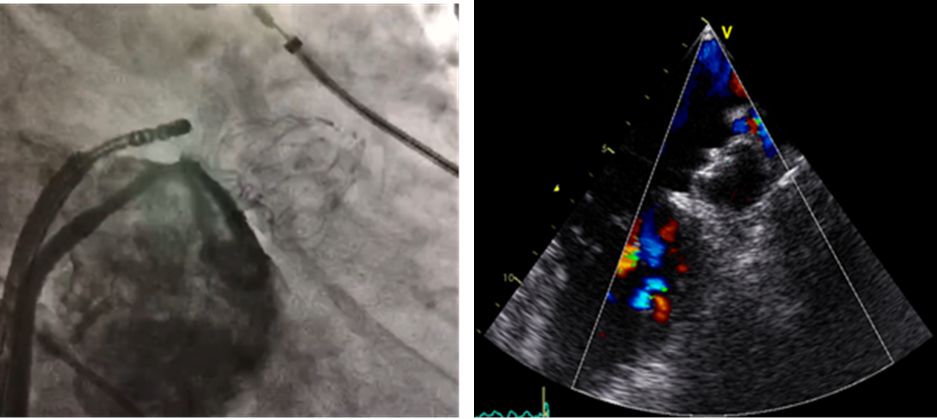

上图为左心耳封堵器植入术后(左:造影图像,右:经食道超声图像)

手术一个小时顺利完成,患者术后恢复良好,此次手术是周陵主任医师团队完成的第50例左心耳封堵手术。 目前该手术量在南京地区排名第一。